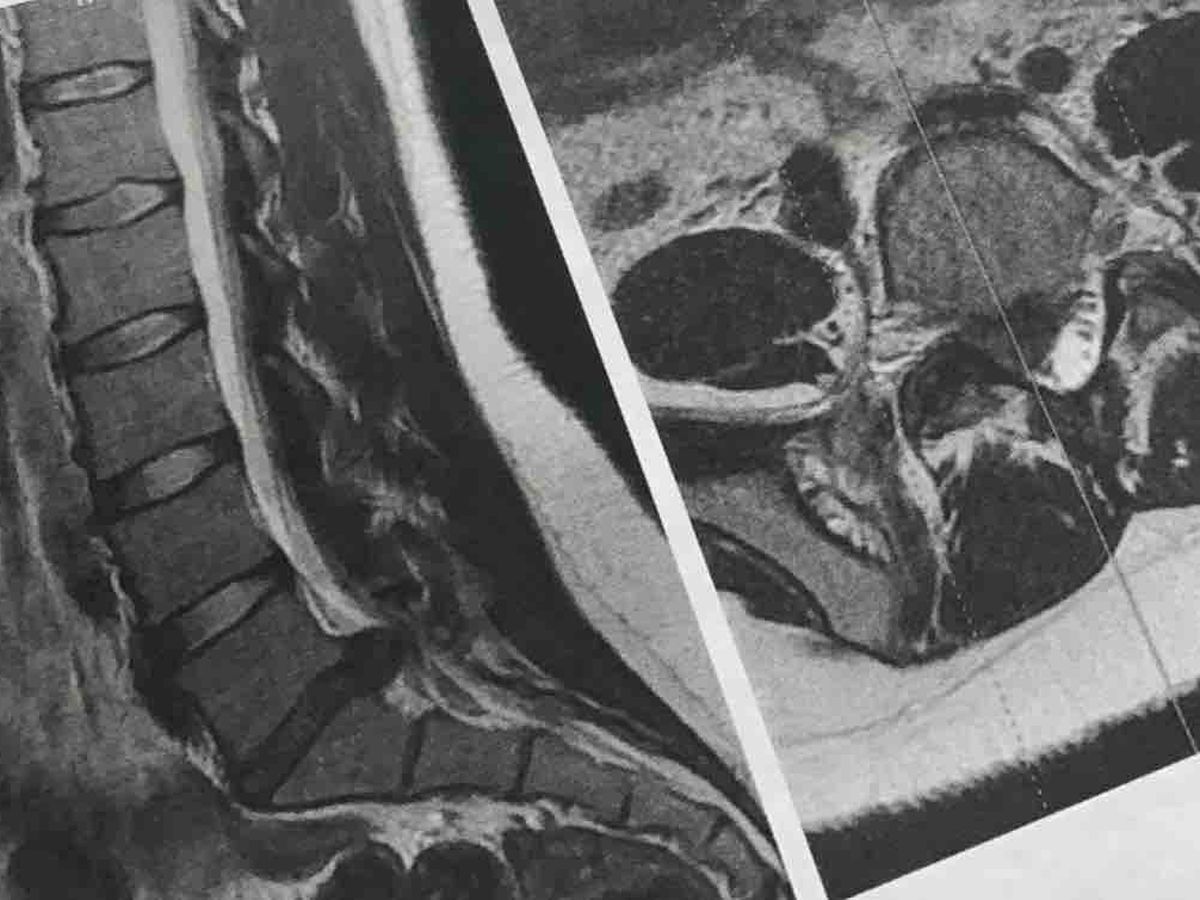

About a month and a half ago, I woke up one day not being able to move without being in excruciating pain. I ended up going to the ER and getting a MRI done.

I have a pretty bad herniated disc (my L5-S1 disc) that's been putting a huge amount of pressure on the nerve that runs down my leg & forcing stenosis. I'm only 20 years old.